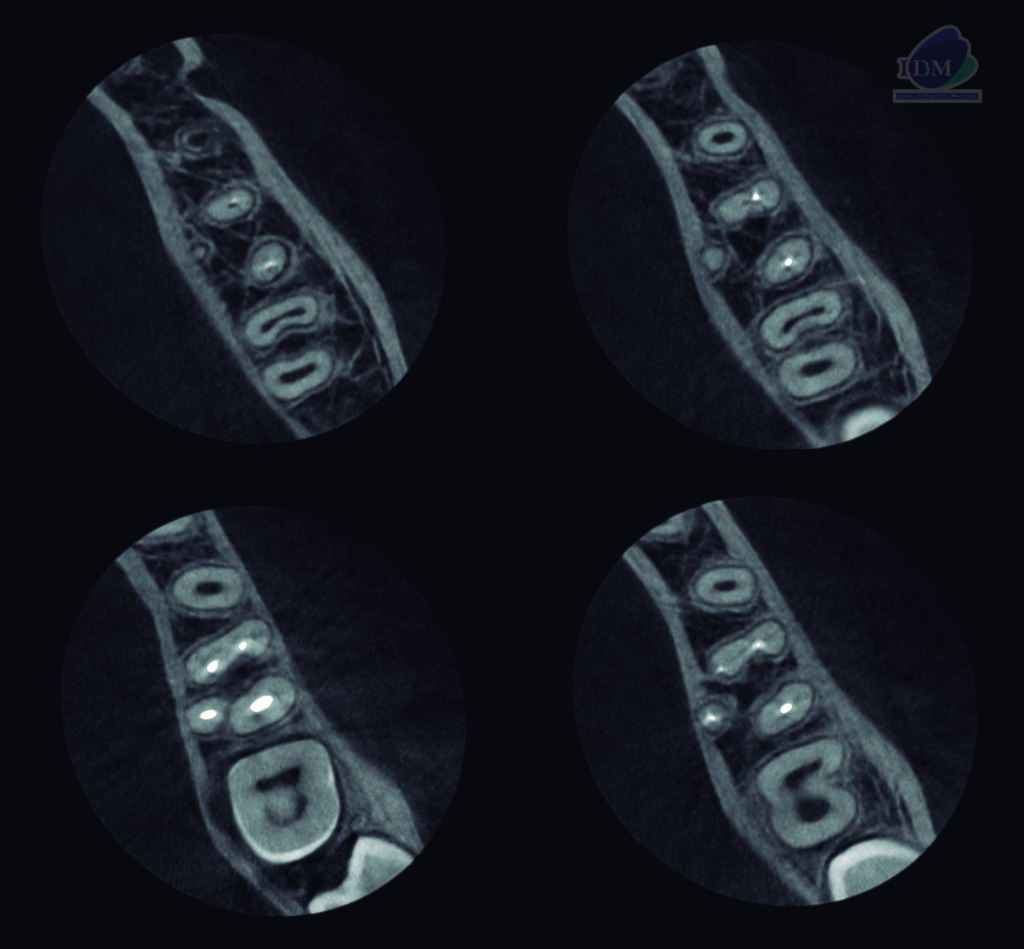

A la evaluación de la tomografía volumétrica (CBCT) en los cortes axiales (Figura 2) y transaxiales (Figura 3), se aprecia marcada dilaceración de raiz supernumeraria en lingual de la pieza 36 que ocasiona el adelgazamiento de la tablo osea lingual. signos tomográficos compatible con radix entomolaris.

CORTES AXIALES

CORTES TRANSAXIALES